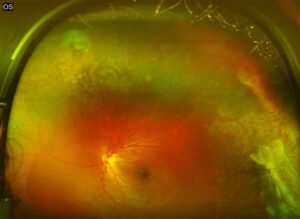

5. Fundus Examination: Examination of the fundus (the interior surface of the eye) can reveal swelling of the optic nerve head (papillitis) or pseudoedema of the optic disc, particularly in the early stages of the disease.